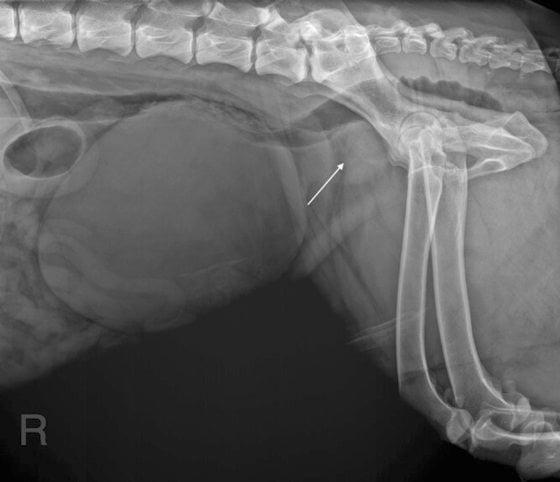

旺旺是一只上了年纪的狗狗,开始时频频排尿困难还有血尿,给了药物后缓和了下来,过后问题又再出现。阿华被逼常常带着它往兽医所跑,钱包大出血外,旺旺的健康状况似乎没有改善,不久前还有排便困难的问题。这些症状来来回回几个月了,我们怀疑没有结扎的旺旺前列腺出现了问题,就连忙吩咐阿华带狗狗前来住院做更进一步的检查,例如直肠触诊、X光、超声波以确定病因,并制定治疗方案。

话说回来,狗狗旺旺在政府兽医所进行了X光扫描,果然证实了前列腺发炎症。在经过结扎手术和药物治疗后,终于痊愈了,彻底摆脱前列腺问题的干扰,阿华头顶上的阴霾也终于烟消云散。